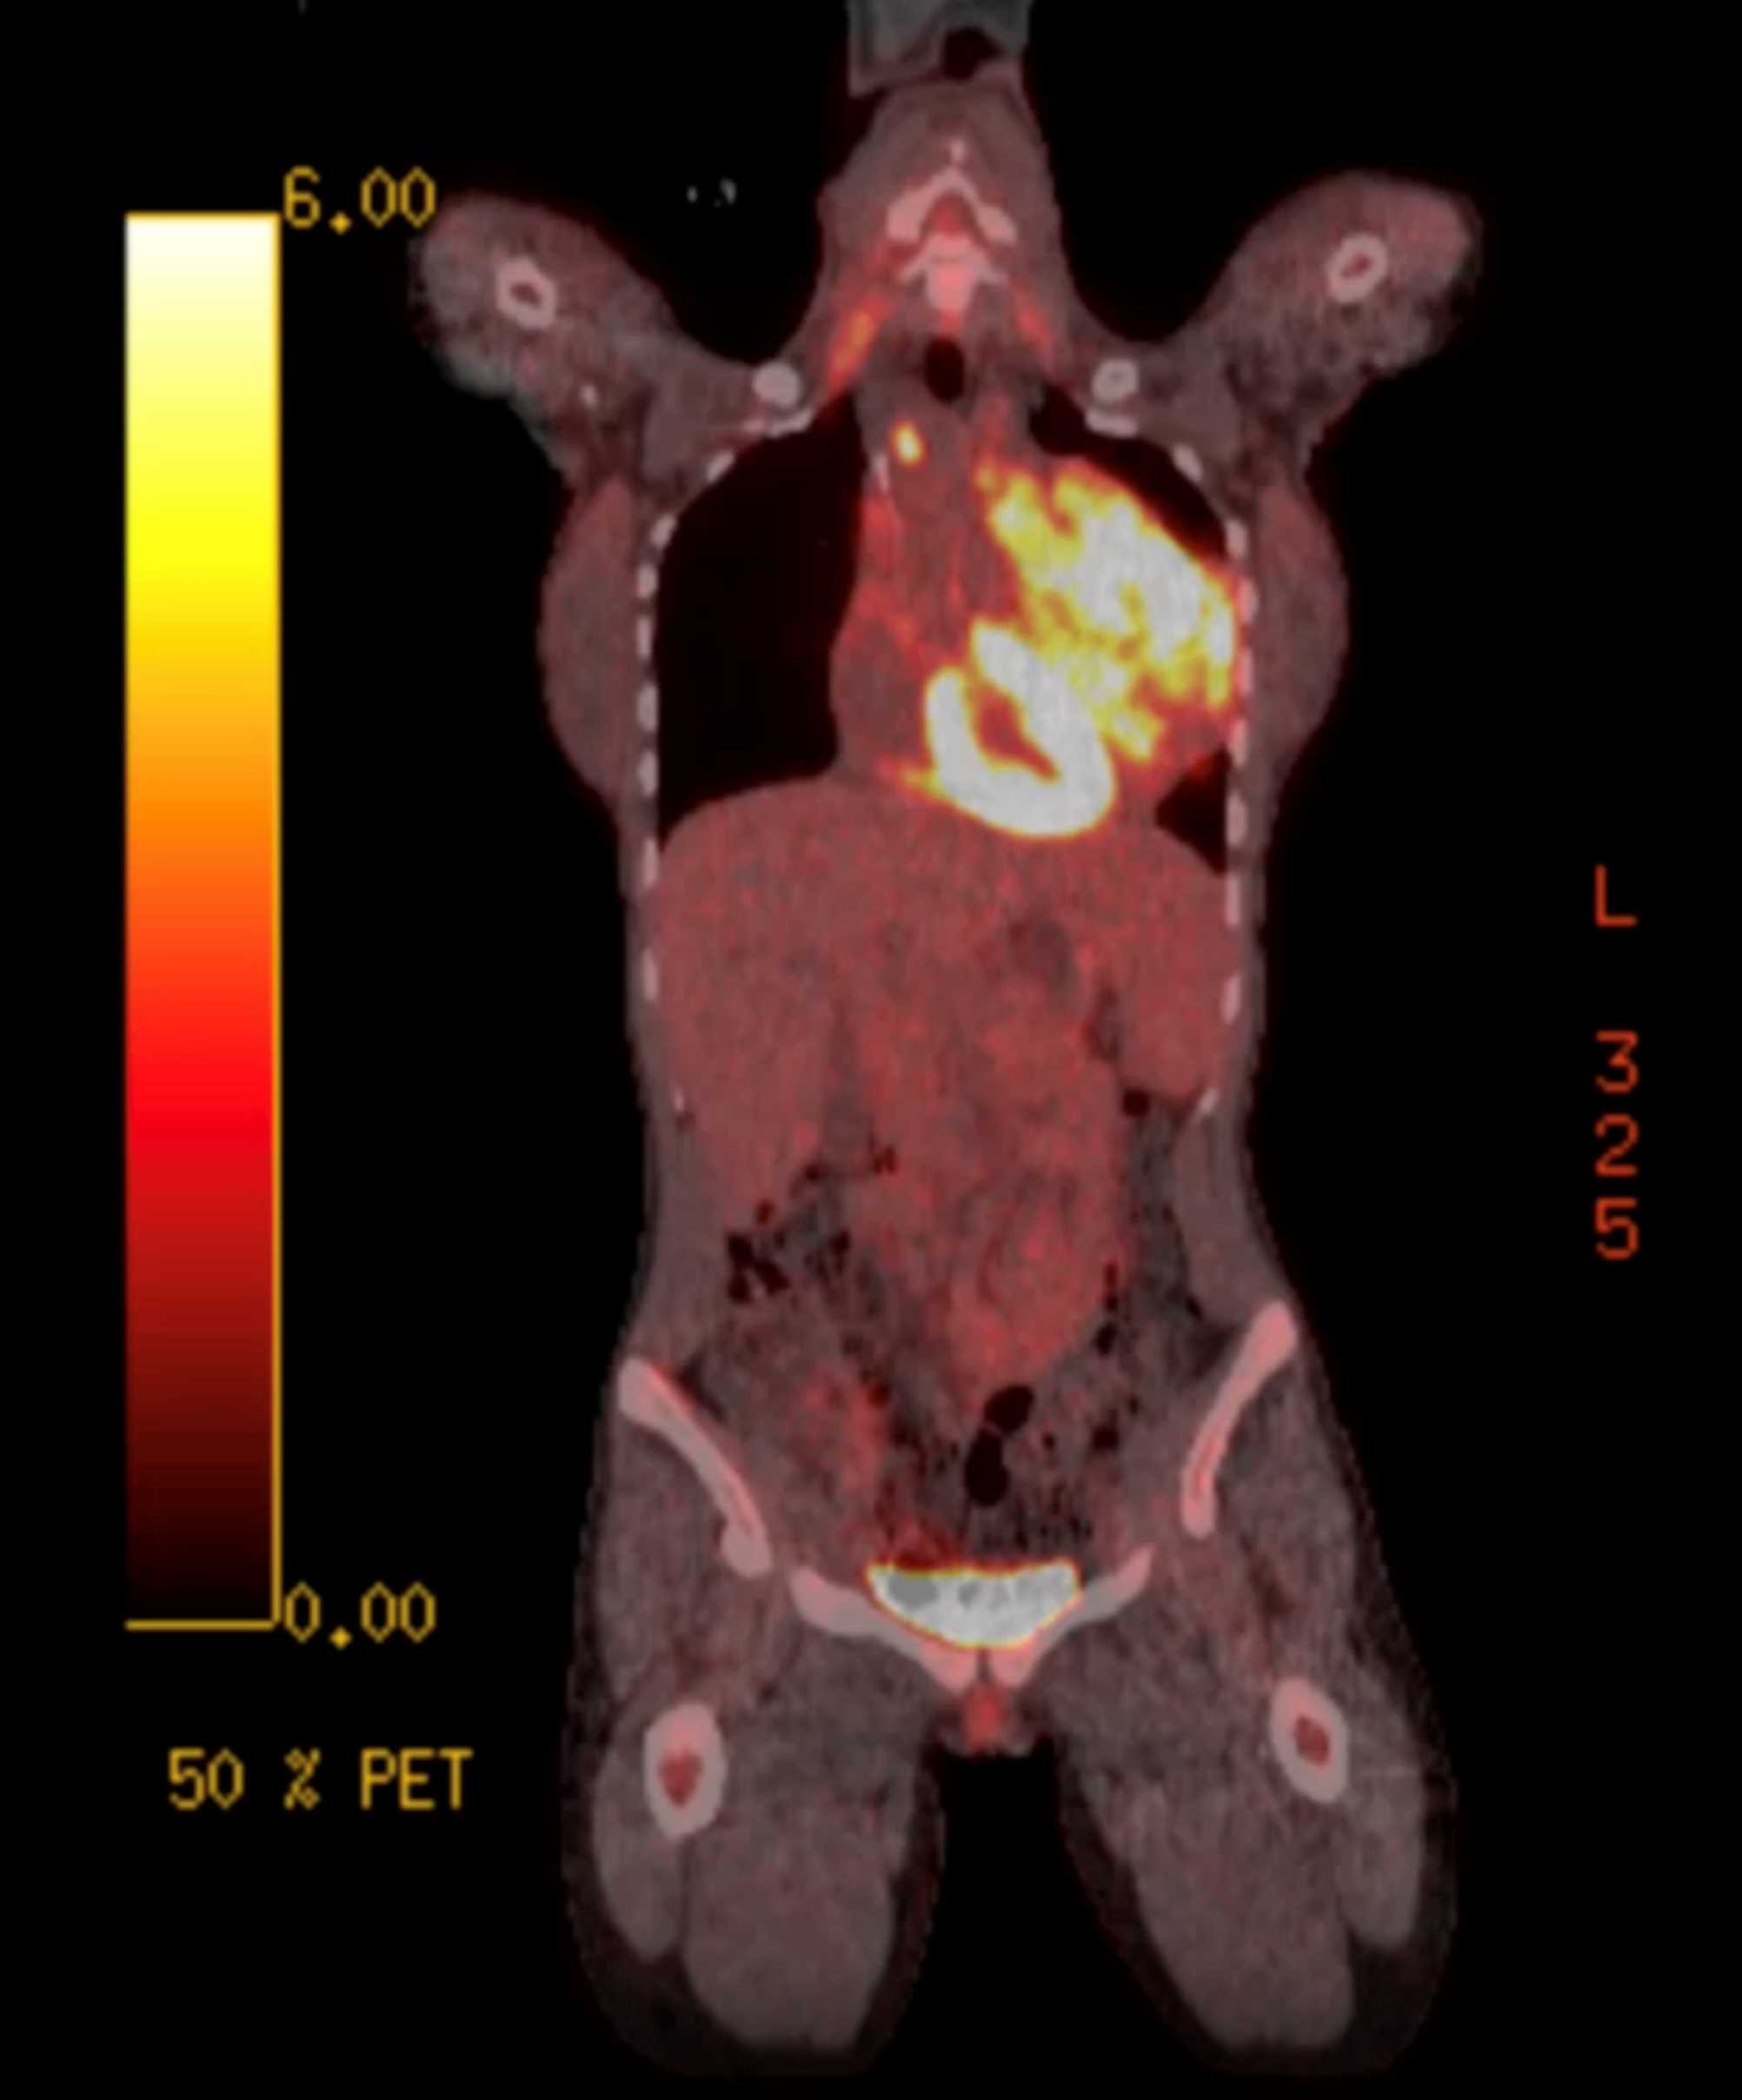

Subtle Adenocarcinoma Pancreas